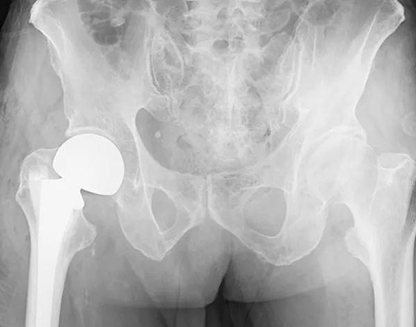

根据老人的身体状况,手术越早进行越好,王鲁博利用周末休息时间为老人实施手术。在麻醉手术科主任张孟元指导下,副主任医师马金本利用床旁B超定位,精确地进行了股神经、股外侧皮神经、髂筋膜和坐骨神经的阻滞麻醉,让老人在清醒条件下暂时失去了右下肢的痛觉。王鲁博带领医疗小组利用X线摄片和手术室透视设备精准确测量需要更换的假体大小和长度,精确到毫米的测量可以确保置换假体的肢体与对侧健康肢体完全等长。在手术室茅金宝护士长的积极配合下,手术顺利完成。

王鲁博介绍说,随着人口老龄化趋势的加快,老年人髋部骨折即股骨颈骨折和粗隆间骨折也越来越多,这种由一次简单的跌倒引发的骨折,常常因骨折后长期卧床出现的并发症短时间内夺去老人的生命,过去常被人们称作“人生的最后一次骨折”。目前创伤骨科已常规开展老年髋部骨折的手术治疗近千例,依靠完善的术前准备,严谨细致的术中操作,尽可能避免全身麻醉,严密的术后观察确保了手术圆满成功。特别是针对股骨颈骨折在常规股骨头置换的基础上,进一步开展术前术中精准测量,保证手术肢体与正常肢体完全等长,取得良好成效,受到患者及家属的高度赞扬。